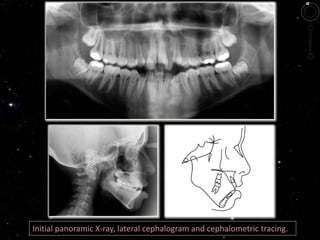

She had a Class I skeletal pattern (ANB=3°), with a good maxillo-

mandibular relationship (SNA=82 ‫؛‬and SNB=79°). She had a Class I

dental malocclusion, bimaxillary protrusion, upper and lower anterior

crowding, with discrepancy of -11.2 mm and -5.5 mm, respectively.

Her incisors were in an edge-to-edge relationship, proclined

(1-NA=28°, 1-NB=36°).

Initial panoramic X-ray, lateral cephalogram and cephalometric tracing.

Initial panoramic X-ray,lateral cephalogram and cephalometric tracing.